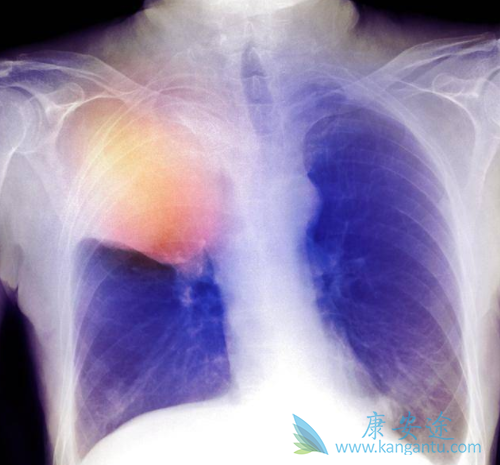

作为全新一代的ALK抑制剂,Lorlatinib的优势在于:患者在接受了多种其它ALK抑制剂治疗耐药之后,Lorlatinib还可能有效,可大大延长患者的生存期!一项Ⅱ期临床试验纳入了275例ALK+或ROS1+晚期NSCLC患者,大多数患者都具有脑转移并且都进行过ALK类药物的治疗甚至是化疗,采用劳拉替尼100mg qd治疗,分析整体ORR以及脑部病灶的ORR。

对于30位初治的ALK阳性患者来说,一线直接使用Lorlatinib治疗:27位患者肿瘤明显缩小,有效率90%,颅内总缓解率为75%;2位患者肿瘤稳定不进展,疾病控制率97%。对于59位使用过克唑替尼或者克唑替尼+化疗的患者来说,Lorlatinib作为二线或者三线药物使用,有效率依然高达69%,颅内总缓解率为68%。对于使用过2-3种ALK抑制剂外加化疗的患者,Lorlatinib作为三线甚至五线药物使用,有效率依然有39%,颅内总缓解率为48%。